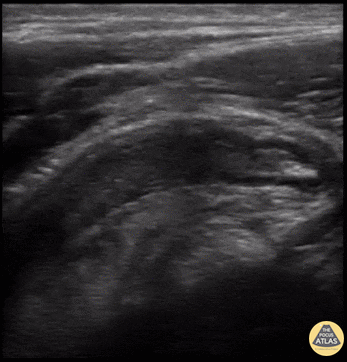

Abnormal appendix in long view, measuring 8 mm in diameter